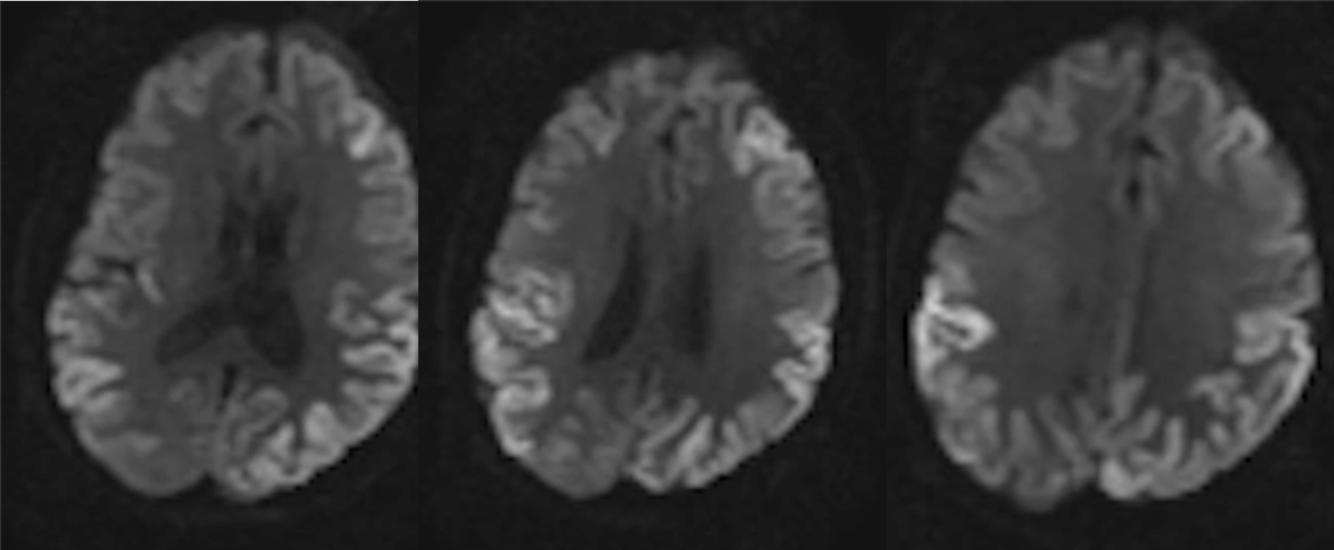

A 65 year-old man presented with the rapid-onset rapid progression of dementia and myoclonus.

Creutzfeldt-Jakob Disease (CJD) with cortical ribboning

A 65 year-old man with dementia.

Creutzfeldt-Jakob Disease (CJD)

MRI